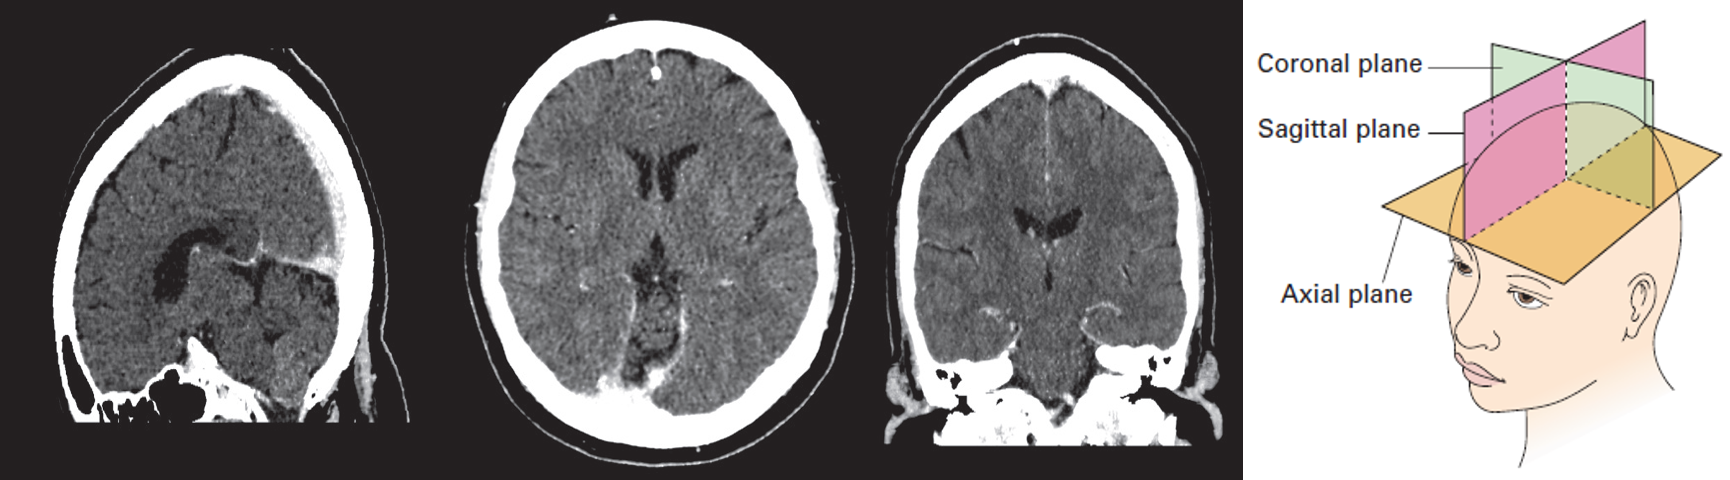

Diagram of the axial, coronal and sagittal planes Corresponding CT images of normal brain